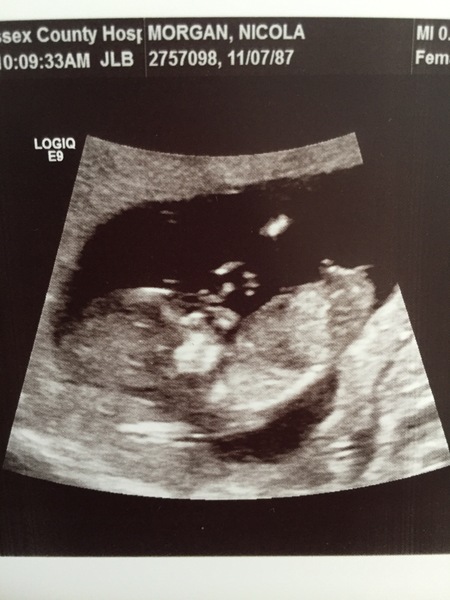

Thanks :-) Mine was sent of at 7 weeks